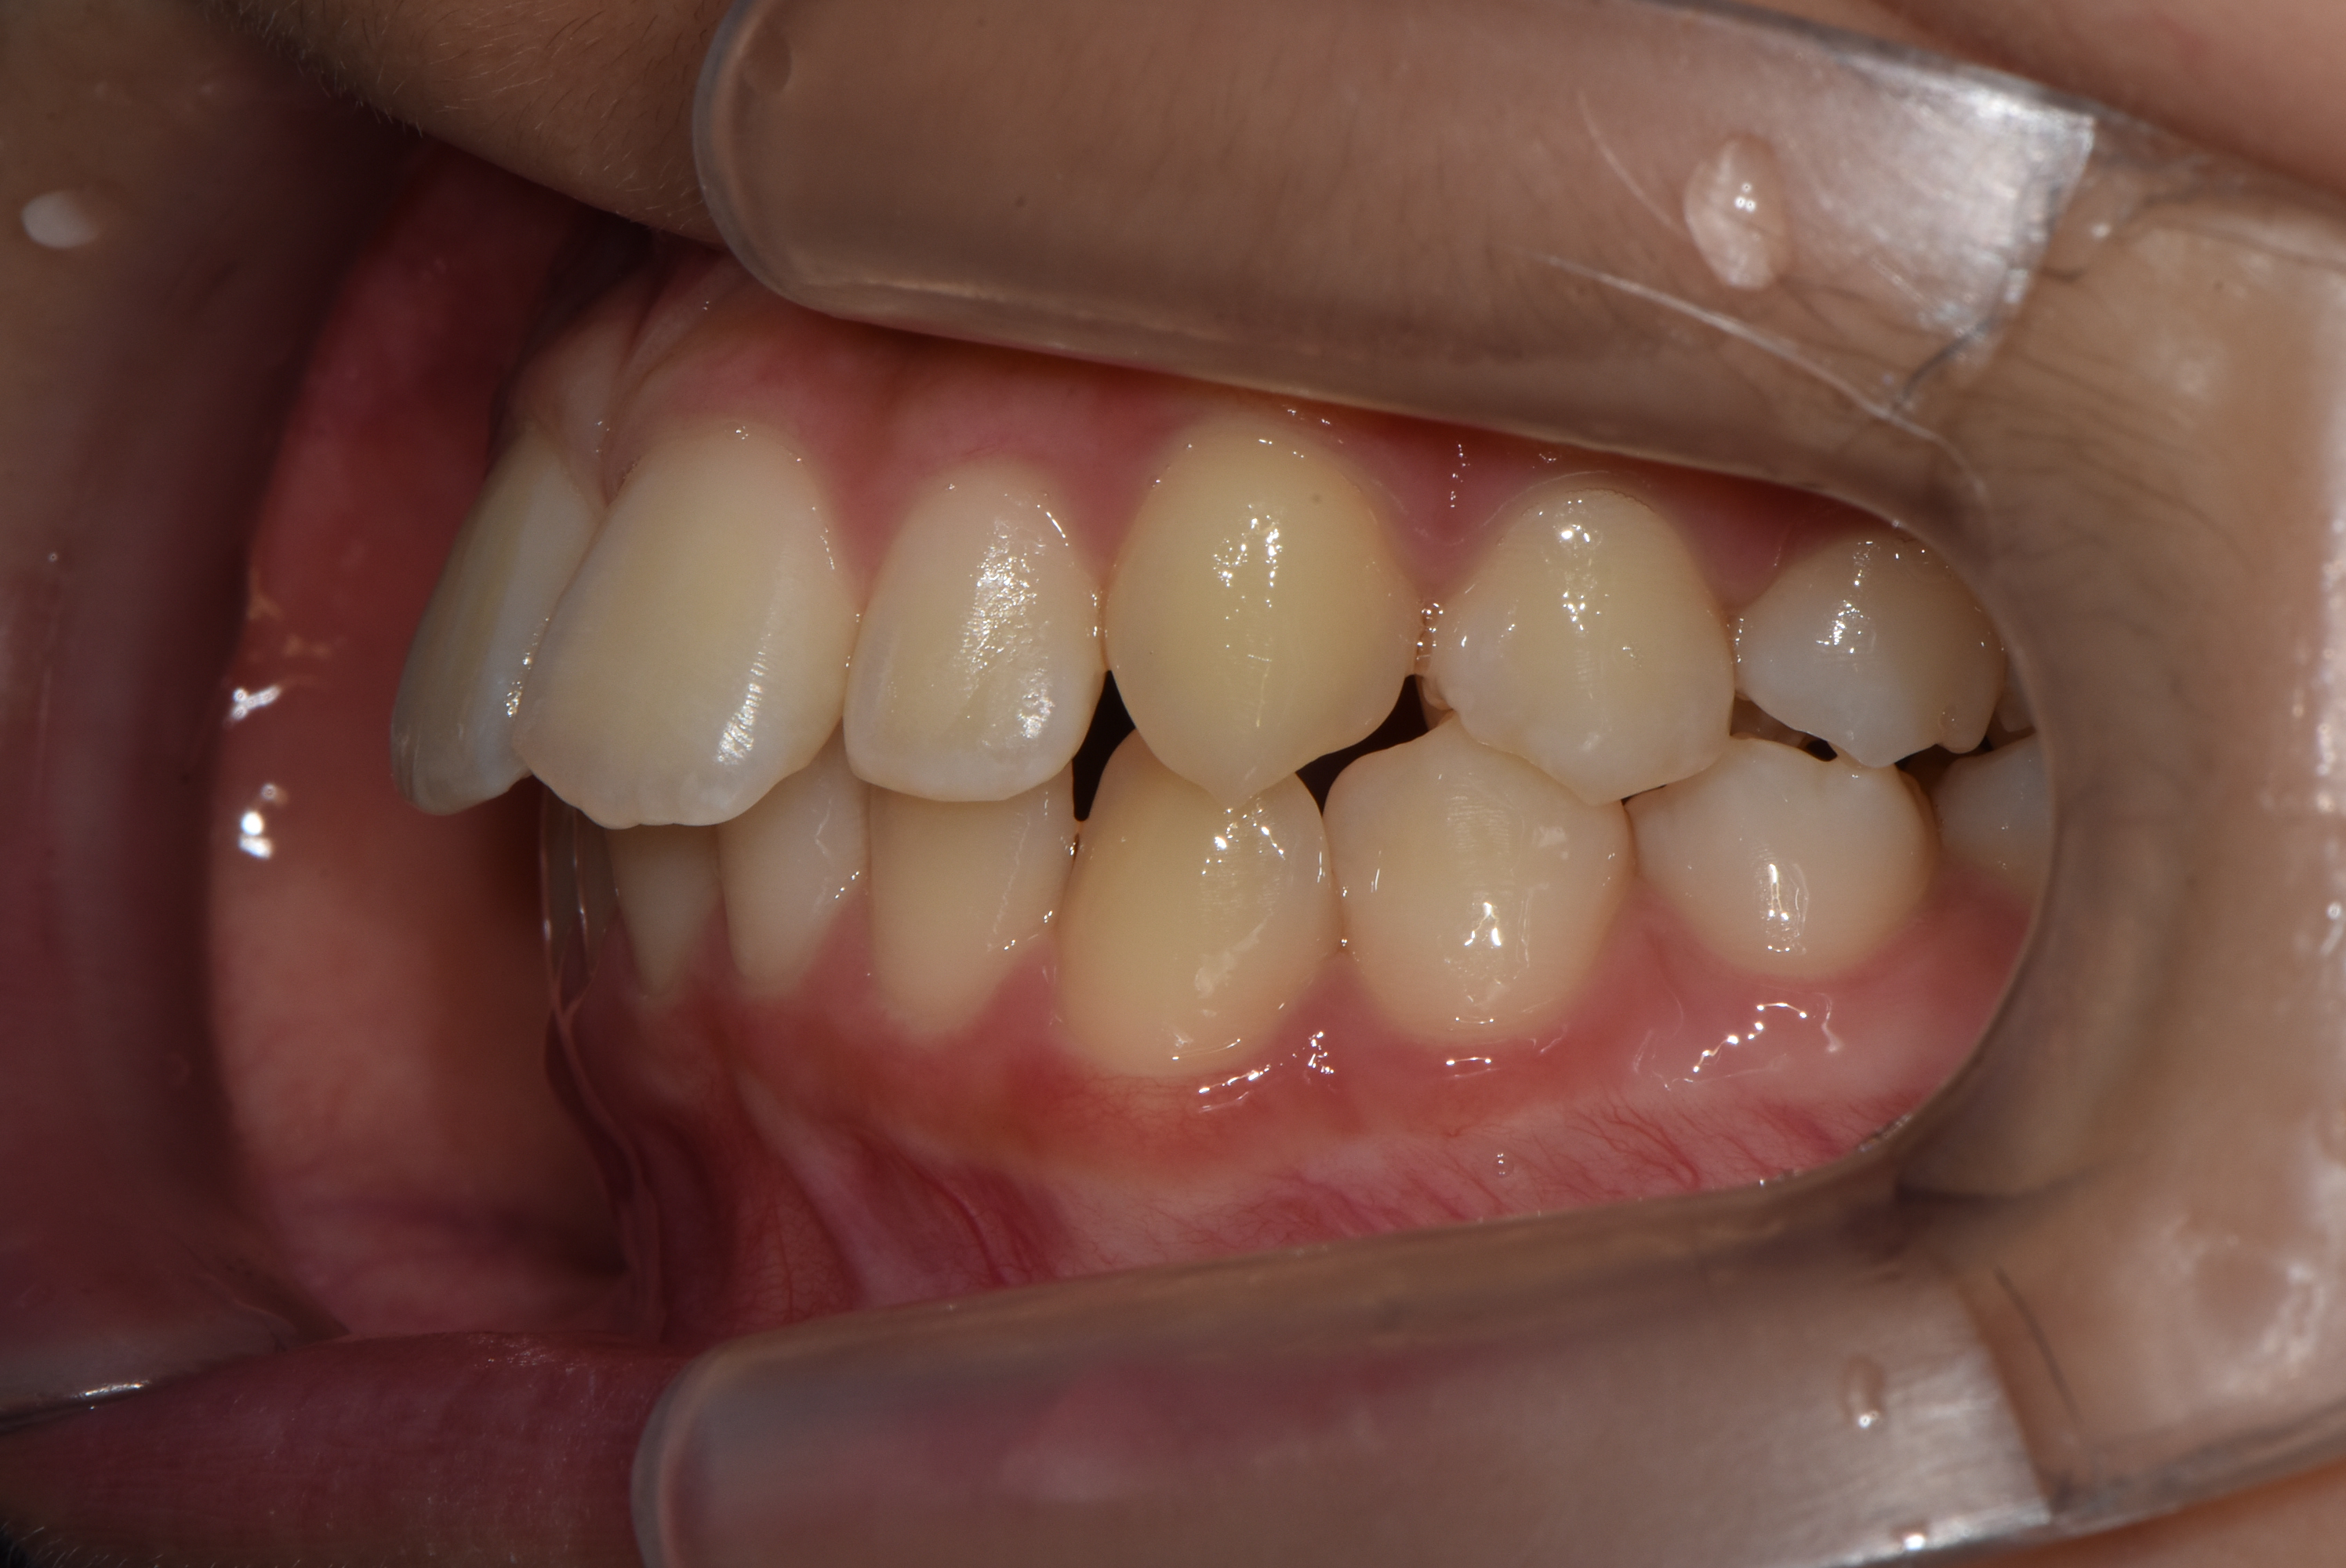

치료 전 사진입니다.